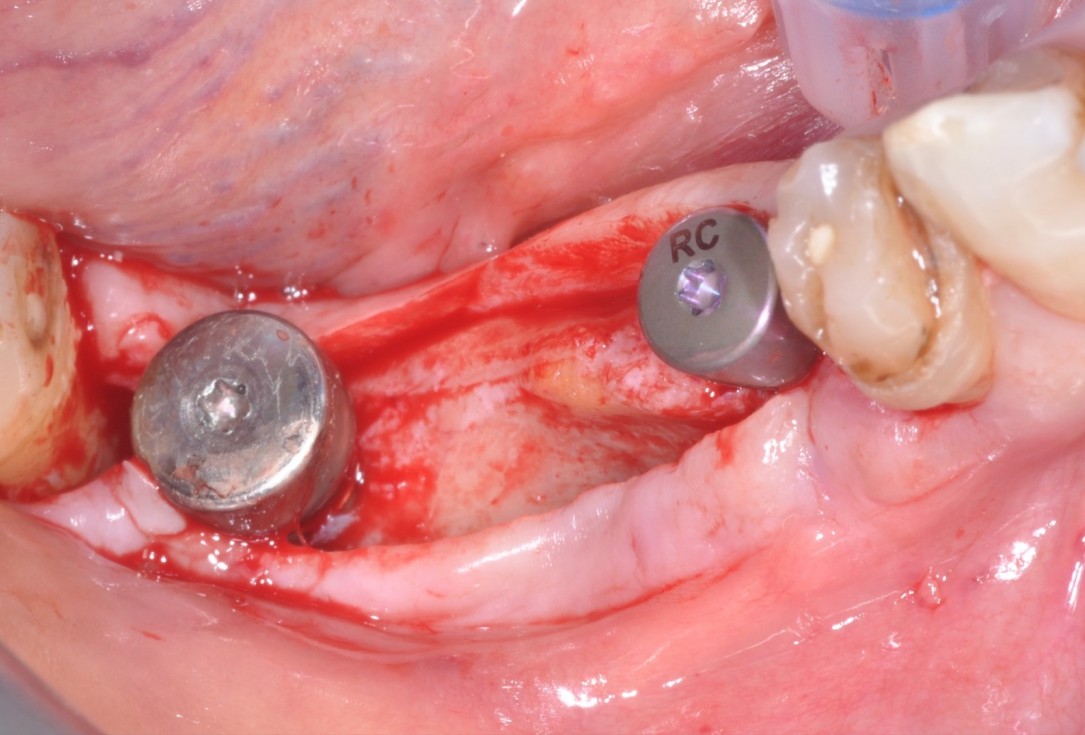

3/9 - Primary stability of two placed Straumann® BLT implantsPeri-implant soft tissue augmentation for pontic with mucoderm® - Dr. M. Frosecchi